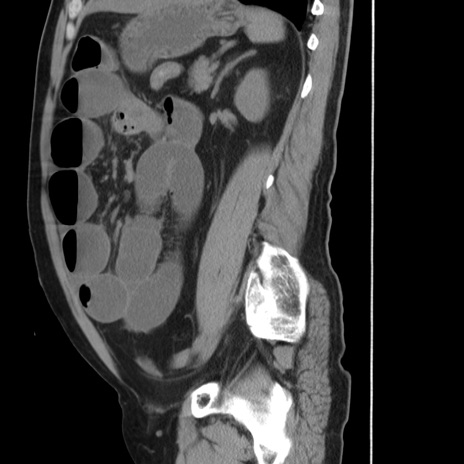

症例20(矢状断像)

【症例】 60歳代男性

【主訴】 腹部膨満、嘔吐

【現病歴】5日前頃より倦怠感を認め食事量減少し4日前の朝嘔吐、食事摂取困難となった。 3日前近医受診し点滴施行され整腸剤などを処方された。 当日他院を受診し、腹部膨満著明、炎症反応の上昇(CRP10.8、WBC11200)あり、紹介受診となる。

【身体所見】 意識JCS1 受け答えがはっきりしないBP 111/57mHg、 P 67bpm、、BT35.2°C、SpO2 97%(RA)、 腹部:膨隆、打診で鼓音あり、全体的に圧痛有り、腸蠕動音(-)、反跳痛ははっきりせず。

【データ】WBC 11400、CRP 14.20